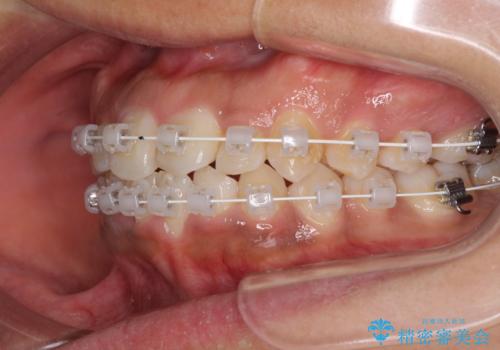

インビザラインが続けられない ワイヤー装置での矯正治療

当初はインビザラインにて治療を開始しましたが、自己管理による治療が難しくなり、ワイヤー矯正へ転換して継続しました。

2年ほどインビザライン矯正を続けましたが、終了することができず、ワイヤーへ転換後は1年弱で終えることができました。